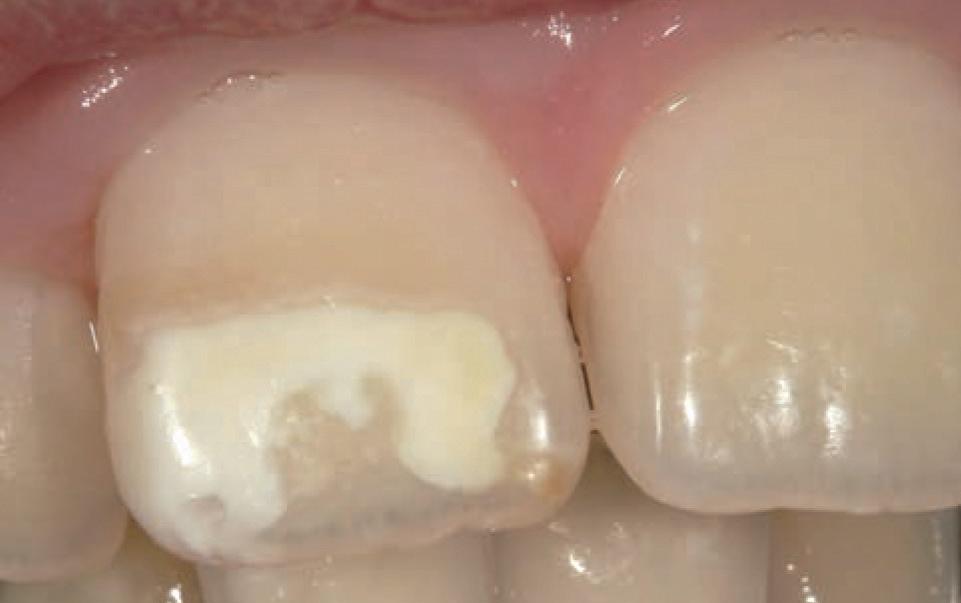

Figure 4. Maxillofacial surgery. Figure 6. TMJ analysis. Figure 8. Airway analysis. Figure 10. Periodontics. Figure 5. Orthodontics. Figure 7. Implant placement. Figure 9. Prosthodontics. Figure 11. Endodontics.